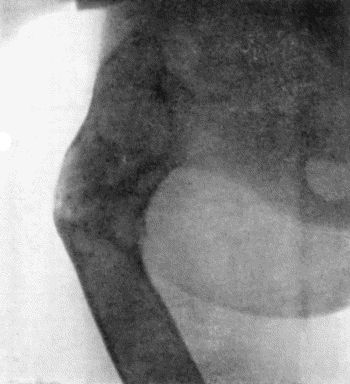

73.Radiogram of Innominate Aneurysm after Treatment by Moore-Corradi method 309

74.Thoracic Aneurysm threatening to rupture 313

75.Innominate Aneurysm in a woman 315